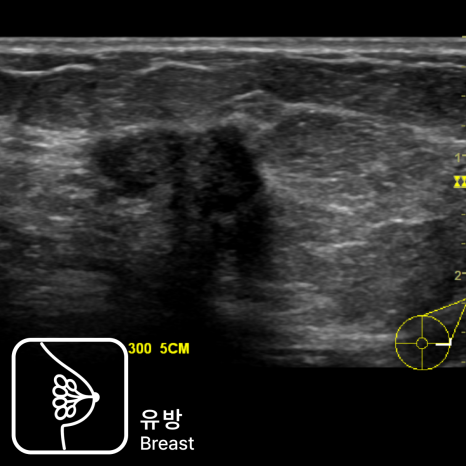

유방초음파에서 환자가 불편감을 호소한 부위에 약 1.5cm 크기의 저에코성 종괴가 관찰되었습니다.

병변은 경계가 불규칙하고 내부 에코가 비균질하며 후방 음영이 동반되어 악성을 강하게 의심하였습니다.

초음파 유도하 유방 조직검사 결과 침윤성 유방암(Invasive Ductal Carcinoma)으로 진단되었습니다.